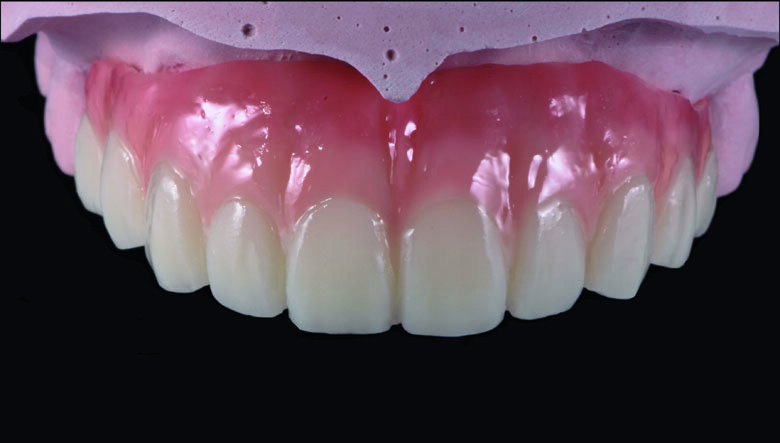

Fig 8. Full-contour waxing was made according to teeth proportion and position.

Fig 12. cutback was made to create gingival space for pink composite layering.

Fig 13. CeraResin bond 1 and 2 (CRB1 and CRB2) were applied to bond the Ceramage pink composite.

Fig 14. Ceramage GUM Opaque (GUM-O) was applied to mask the color of PMMA.

Fig 15. Ceramage GUM Dark (GUM-D) was applied on the attached gingiva area to the buccal flange

Fig 16. Ceramage GUM light (GUM-L) was applied in order to imitate the free gingival area.

Fig 17. Ceramage Flowable GUM Red (F-GUM-R) and White (F-W) were painted to mimic the mucogingival junction and vascular alveolar

Fig 18. Ceramage GUM translucent (GUM-T) was applied to reproduce of reddish translucent gingiva areas.

Fig 19. Completed Provisional Profile Prosthesis with gingival aesthetics that mimic nature

Preparation cast with a diagnostic wax-up ca st was sent to a local laboratory for scanning and transforming into STL (Stereolithography) digital impression file. (Fig 8,9.) Two sets of STL impressions were super-imposed in the software in order to subtract the overlapping data. This process was done in order to transform the diagnostic wax-up into the STL digital impression. Consequently, the STL data was sent to the laboratory for milling. (Fig10.) A monochromatic milled-PMMA temporary bridge was fabricated in a local laboratory and returned to the dentist for composite layering. (Fig 11.) Gingival cutback was made to create sufficient gingival space for pink composite layering (Fig 12). Prior to composite layering CeraResin Bond 1 was applied and left for 10 seconds to prime the surface, followed by application of CeraResin Bond 2 for 10 seconds and light cured for 20 seconds (Fig 13.). Ceramage Indirect Composite gingival shade GUM-O (GUM Opaque) was applied to mask the color of PMMA (Fig 14.). GUM-D (GUM Dark) was applied on the attached gingiva area to the buccal flange (Fig 15.). GUM-L (GUM Light) was applied in the region of free gingiva (Fig 16.). F-GUM-R (Flowable GUM Red) and F-W (Flowable GUM White) were painted to mimic the mucogingival junction and vascular alveolar mucosa (Fig 17.) GUM-T (GUM Translucent) was applied to reproduce of reddish translucent gingiva areas (Fig 18) to achieve natural gingival aesthetics.

Meticulous finishing and polishing of the restoration is a crucial step to achieving the desired aesthetics. Dura-Green stone was used to contour the macro anatomical details while the Robot Carbide Fissure Bur was used to shape the interproximal and papilla areas. The course silicone points followed by Dura-Polishing paste Al2O3 with a medium strong brush was used to finish and pre-polish the restoration. Dura-Polish DIA, diamond polishing paste was applied with a fine brush followed by the cotton buff to achieve the final high-luster polishing (Fig 19.)1.